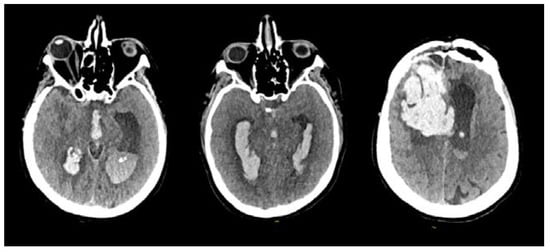

The initial CT scan revealed the presence of an intraparenchymal hematoma combined with intraventricular hemorrhage in all patients (Figure 2). On admission, the median GCS score was 8/15 (ranging from 4/15 to 8/15), necessitating urgent intubation and sedation. Subsequently, a standard frontal EVD was expeditiously inserted. Following EVD placement, all patients exhibited varying degrees of progressive neurological improvement. However, it is important to emphasize that each patient necessitated either one or multiple EVD placements due to catheter blockage. No other complications, particularly meningitis or ventriculitis, were documented throughout the course of treatment.

Figure 2.

Initial CT scans of three different patients showing various intraventricular hemorrhagic extension patterns due to a ruptured bAVM.